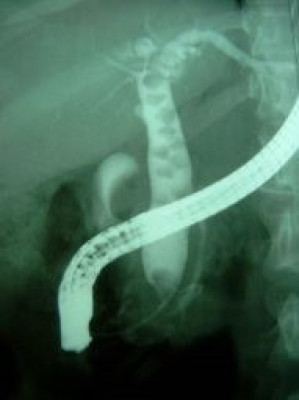

Coledocolitiasis múltiple y extracción

Envíado por Dr. Carlos Miguel Zavaleta Consuegra